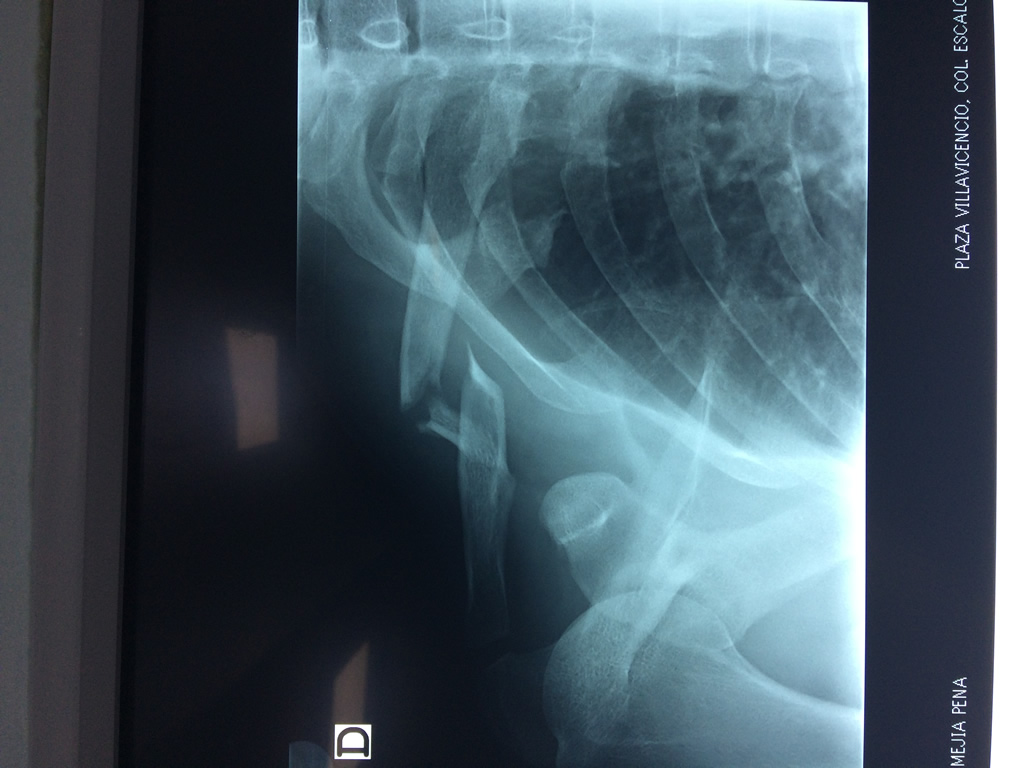

Cirugias en El Salvador - Clavícula